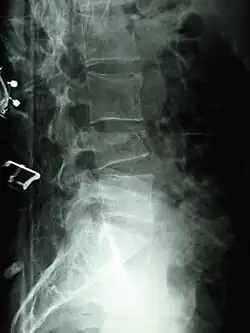

Compression fracture of the fourth lumbar vertebra post falling from a height. -

X-ray of the lumbar spine with a compression fracture of the third lumbar vertebra. -